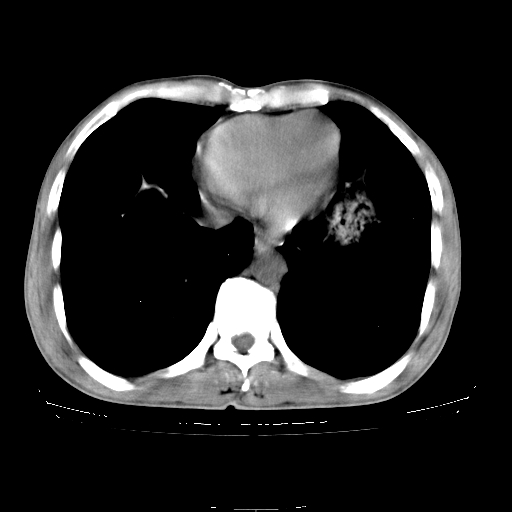

以下是引用yangyudong333在2008-4-29 5:38:00的发言:[br]比较典型的矽肺结节.支持[br]诊断依据:[br] 1.x线表现:[br] ①典型矽肺为多发直径 1~3mm 小结节,即矽结节,由胶原纤维和硅尘构成,可融合成团块,好发于上肺。[br] ②团块周围常有肺大泡。[br] ③胸内淋巴结增大、钙化。如肺门淋巴结呈蛋壳样钙化有助于与其他尘肺区别。[br] ④胸膜常广泛粘连、增厚。[br] 2.ct表现[br] ①两肺散在大小较为一致的小结节影,其密度较高,边界清楚。[br] ②小结节可融合为较大团块影,直径约 1cm ,甚至可达 10cm以上,易发生在上叶。[br] ③小结节周围常并有小叶中心气肿或弥漫性肺气肿。

以下是引用liuyue在2008-4-28 22:30:00的发言:[br]比较典型的矽肺结节.[br]请结合临床及化验除外矽肺合并肺结核之可能.